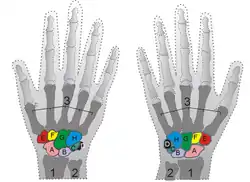

| Shown is the right hand, palm down (left) and palm up (right). Proximal: A=Scaphoid, B=Lunate, C=Triquetral, D=Pisiform Distal: E=Trapezium, F=Trapezoid, G=Capitate, H=Hamate | |